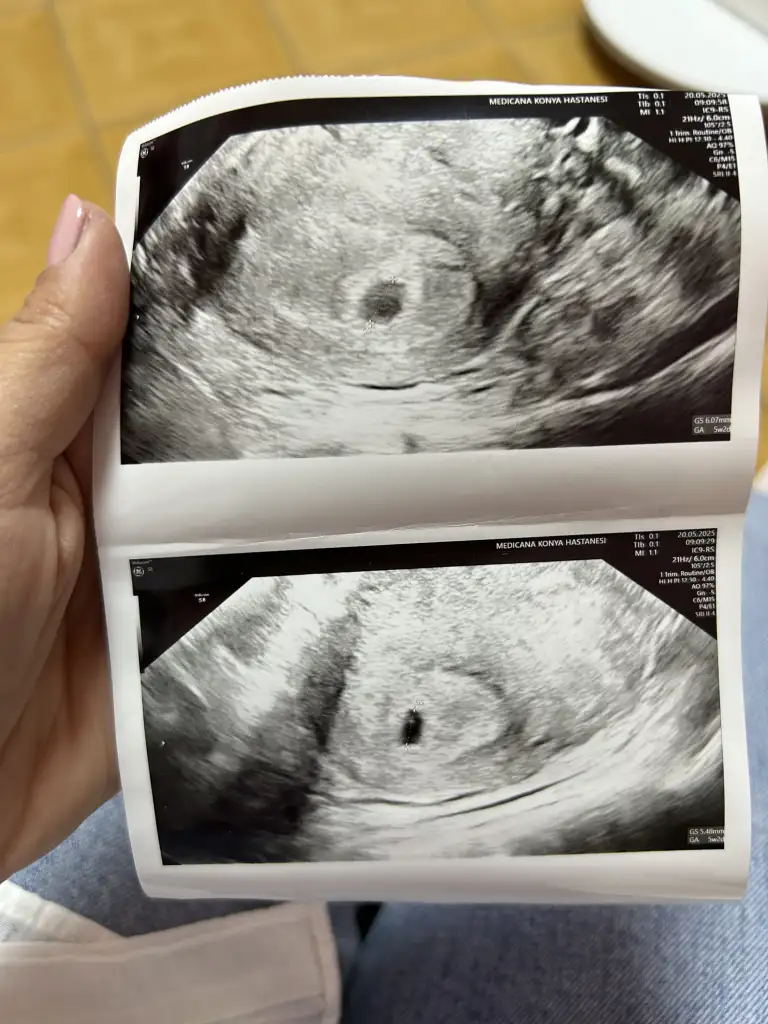

Hayirli olsun canim kac haftaliksin vajinal mi baktilarEki Görüntüle 3593870 Kızlar bugün muayeneye gittim. Keseyi gördük çok şükür. Acaba alttaki fotoğrafta kese içindeki küçük nokta bebek mi oluyor bilgisi olan var mııııı

Evet canım vajinal baktı. Son adet tarihime göre 4+6 ama doktor 5+2 gibi bir şey dedi anlamadım tamHayirli olsun canim kac haftaliksin vajinal mi baktilar